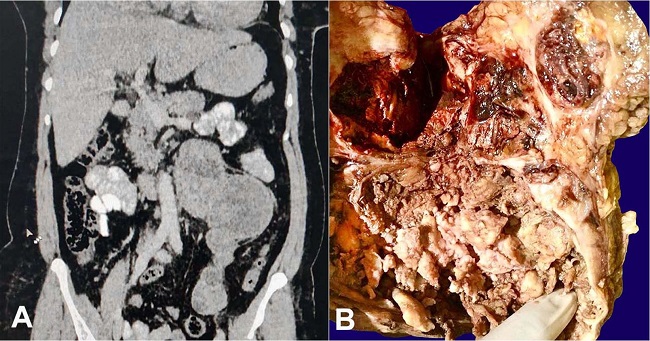

Abdominal-pelvic computer tomography imaging showed a longitudinally oriented heterogeneously enhancing solid cystic retroperitoneal mass measuring 7.2cm x 10.3cm x 19.4cm epicentered near the left kidney (Figure 1A). The mass was compressing the left renal vein superiorly, extending up to left psoas inferiorly, abutting the aorta medially and left renal pelvis laterally, displacing the bowel loops anteriorly and abutting the left ureter posteriorly. The left kidney showed features of hydronephrosis. Uterus and bilateral adnexa were not visualized. The laboratory investigations including metanephrines, normetanephrines, chromogranin, CA -125, CEA, AFP and beta HCG levels were within normal biological range. The patient underwent laparotomy and excision of the retroperitoneal mass. On gross examination, the mass weighed 450gm and measured 8cm x 10cm x 20cm. It was partially encapsulated. The cut surface was solid cystic showing areas of hemorrhage and necrosis. The cysts were filled with clotted blood (Figure 1B).